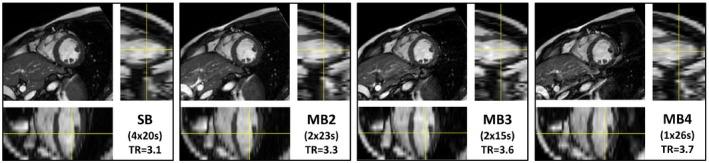

Blipped and RF-cycled CAIPI were implemented into a retrospective-gated segmented cine multiband bSSFP sequence. The 2 methods were compared at 3T using MB2 to demonstrate the effect on frequency response. Further data (4 subjects) were acquired at both 1.5T and 3T collecting 12-slice short axis stacks using blipped-CAIPI with MB acceleration factors of 1-4. The impact on SNR and contrast was evaluated along with g-factors at different accelerations.

Data acquired with blipped-CAIPI multiband bSSFP up to factor 4 yielded functional cine data with good SNR and contrast, while reliably keeping dark-band artefacts clear of the heart at 1.5T. SAR limits the maximum MB acceleration, particularly at 3T, where minimum TR increase is problematic and leakage artefacts are more prevalent. Mean g-factors across the heart were measured at 1.00, 1.06, and 1.12 for MB2-MB4, whereas blood-pool SNR measures (end-diastole) decreased by 11.8, 21.5, and 36.9%; ultimately LV-myocardium CNR remained sufficient at 1.5T with values ranging: 15.6, 13.4, 11.9, and 9.6 (MB1-MB4).